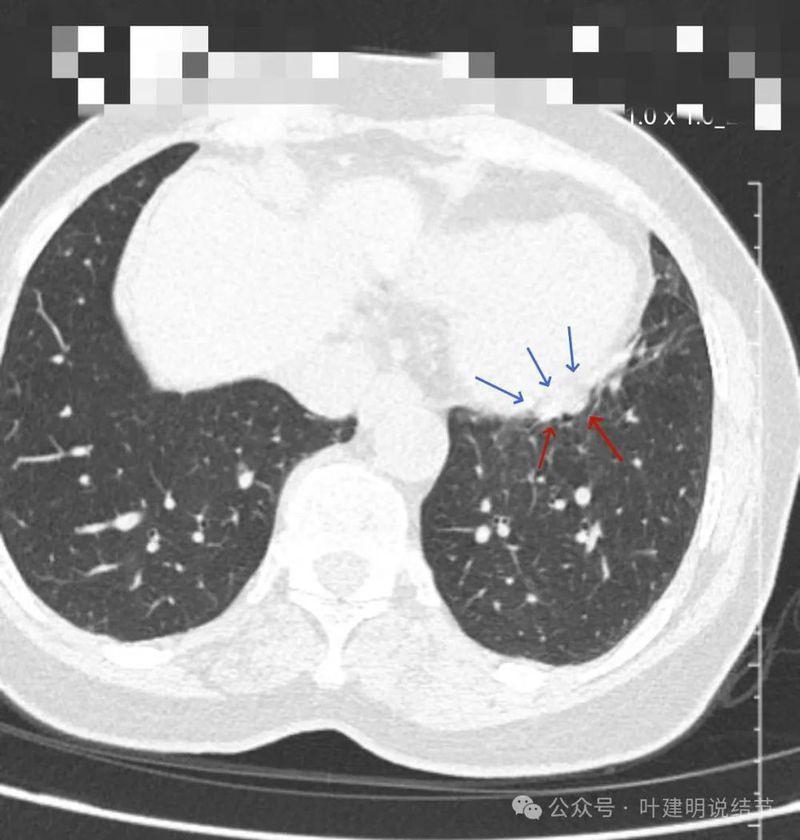

左下实性结节,明显有膨胀感,边缘虽然光滑,但给人感觉不舒服,恶性的可能性大些。

轴位病灶实性,分叶,膨胀!

病灶表面不平,有浅分叶,与膈肌之间有间隙。

与膈肌之间间隙明显,病灶实性,膨胀性明显,边缘相对较为光滑。